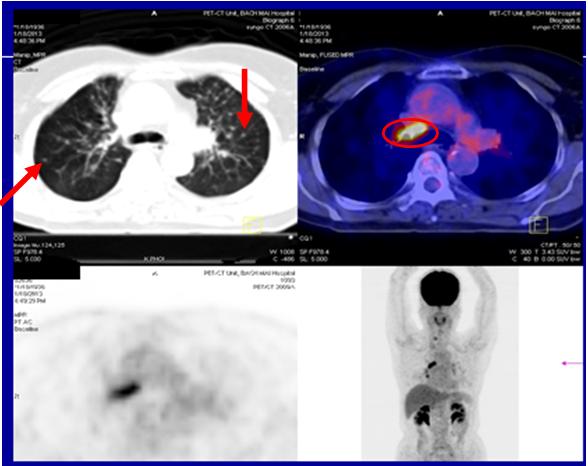

+ Bệnh nhân được tiếp tục duy trì điều trị Erlotinib(Tarceva) hàng ngày, đến thời điểm sau 30 tháng điều trị, bệnh nhân ổn định, chụp PET/CT đánh giá lại: kết quả cho thấy khối U đỉnh phổi phải tan hết, các nốt tổn thương thứ phát phổi trái biến mất.

Hình 2: Hình ảnh u phổi phải tan hết, các tổn thương phổi di căn biến mất.

- Lâm sàng: Bệnh nhân không còn ho ra máu, không đau tức ngực, sinh hoạt bình thường.  Khối u phổi phải và các tổn thương thứ phát tại phổi trái biến mất gần hoàn toàn sau điều trị.